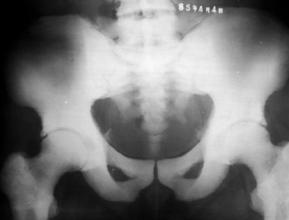

髋关节脱位(股骨和骨盆髋臼之间的关节失去了正常位置)

1.脱位原因:高能量损伤才能脱位,车祸、高坠伤等,发生率约占全身各关节脱位的5%,85%-90%为后脱位,多发生于青壮年

2.脱位分型:以髂坐线(Nelaton:坐骨结节至髂前上棘的连线。正常情况下,此线经过大转子尖端,当股骨颈骨折或髋关节后脱位时,大转子尖端可向上移位超过此线。)为标准:前方——前脱位(外展位);后方——后脱位(内收位);中心脱位:股骨头突破髋臼底部或入盆腔(合并有髋臼横行骨折,或髋臼顶骨折或者髋臼复杂性骨折,并入髋臼骨折处理)

3.临床表现:1、外伤史,2、肿胀、疼痛、髋关节活动受限,后脱位:患者缩短;髋关节屈曲、内收、内旋(弹性固定),黏膝征(+),前脱位:患肢增长;髋关节屈曲、外展、外旋(弹性固定),黏膝征(-),中心性脱位:股骨头严重移位者,大粗隆内移,患肢短缩。

沈通氏线(Shenton’s线):是指正常骨盆X线中耻骨下缘弧形线与股骨颈内侧弧形线连成的弧度。